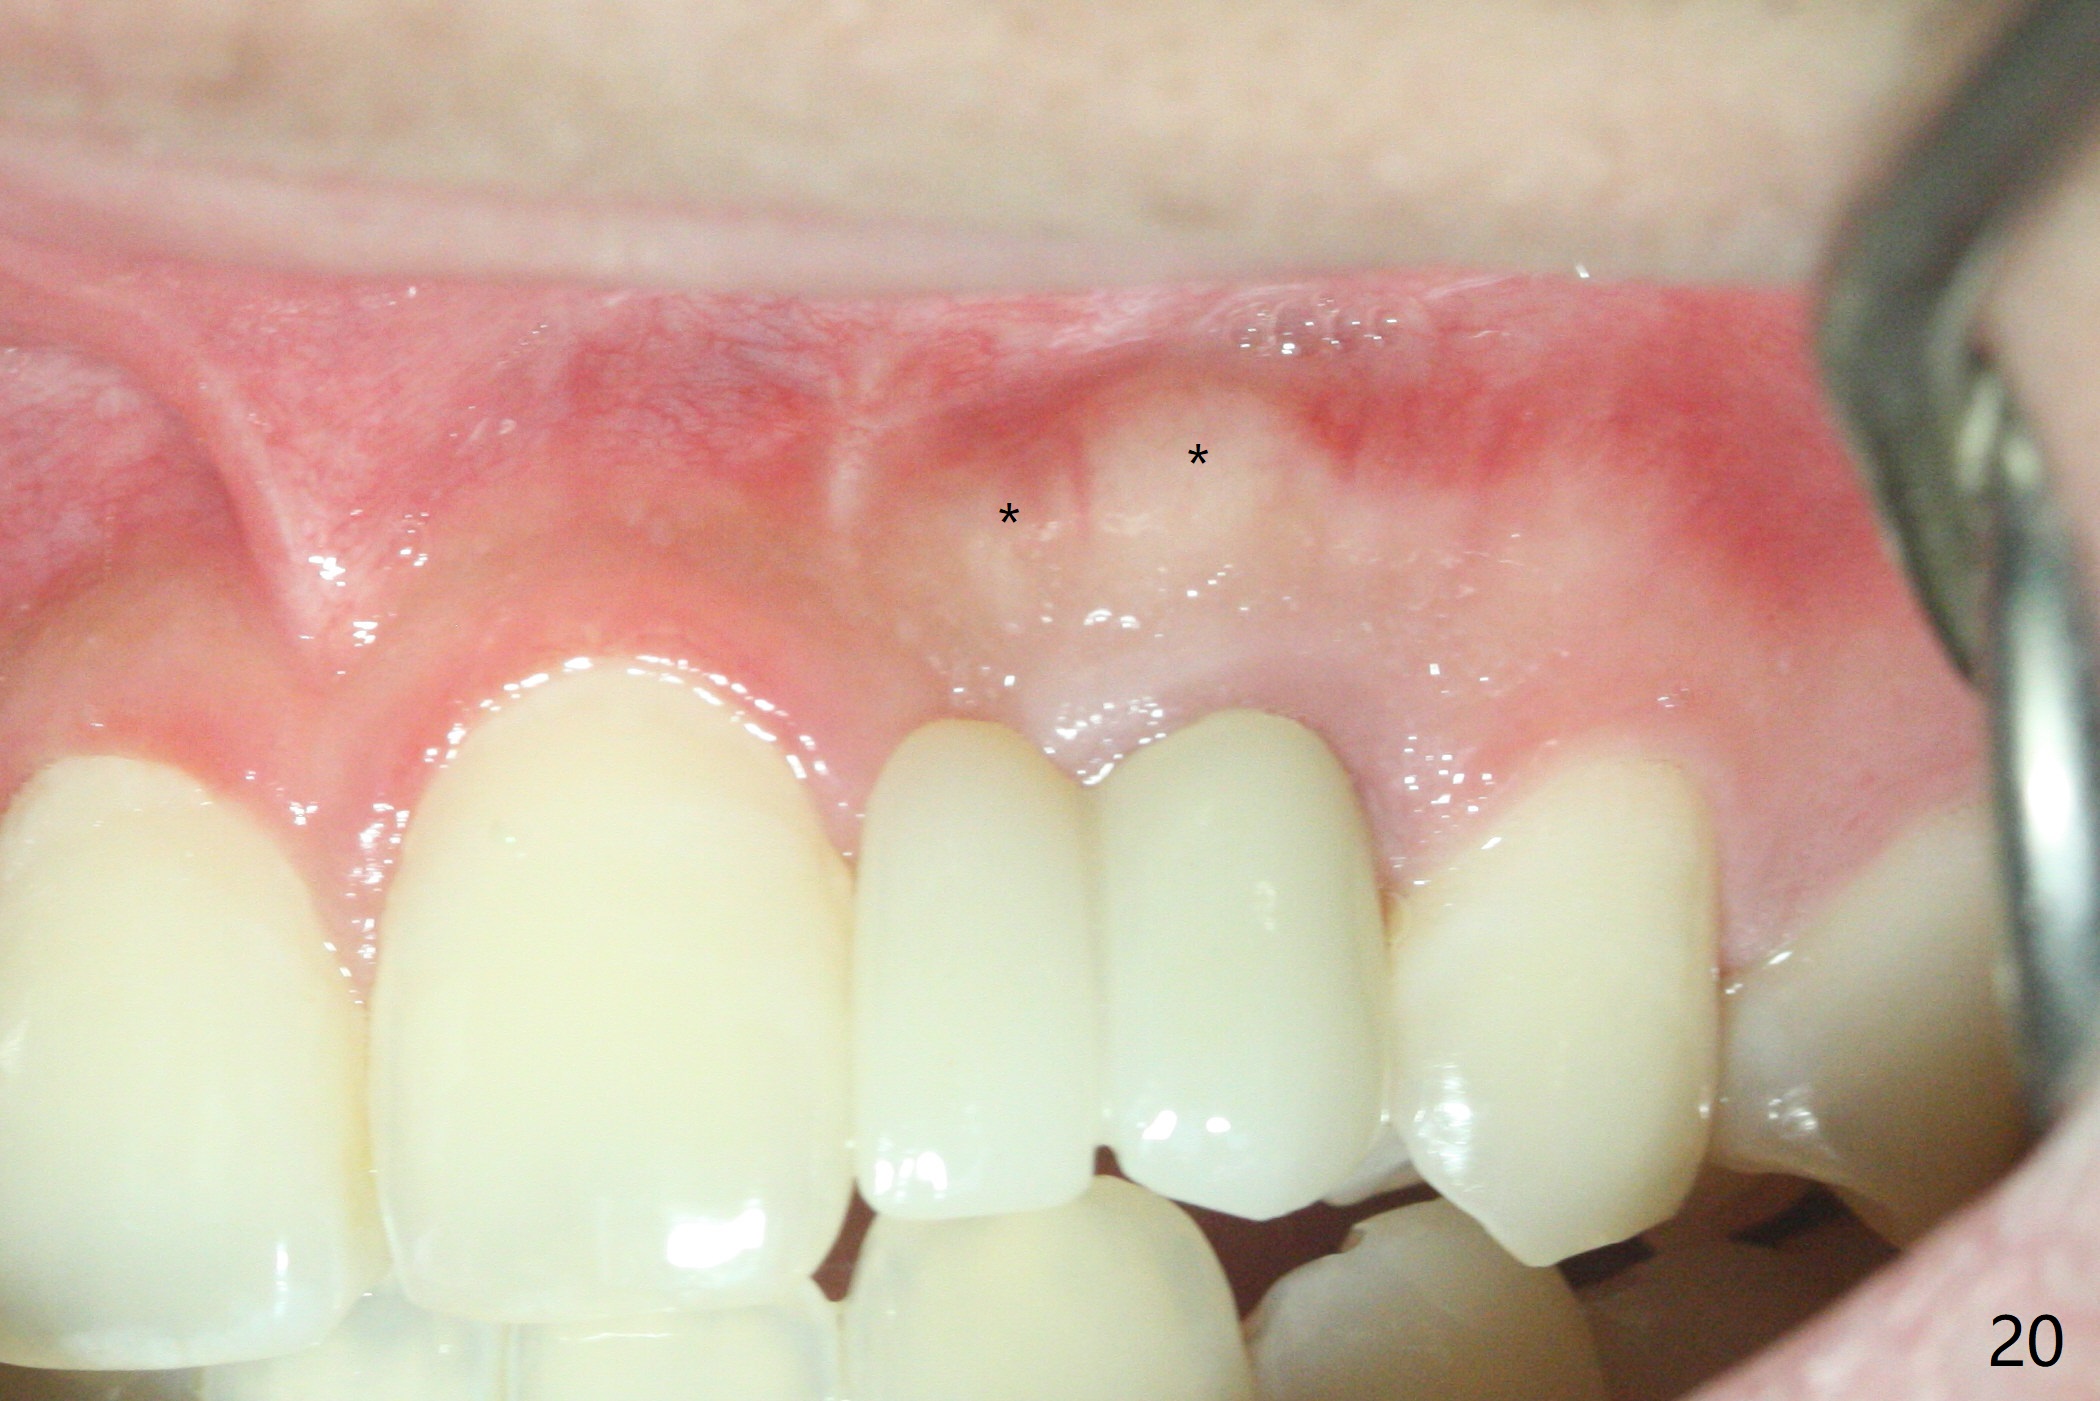

18岁男从外州大学回来,无症状,但是6号牙(右上尖牙)颊侧瘘道(图一,二(角化龈充分(箭头))),根尖片显示植体近中骨吸收(图三:*),而对侧植体仿佛骨整合(图四)。患侧切开后发现植体颊侧暴露,松动。拔除后骨缺损由粘性骨粉修复(图七,九:*),覆盖PRF膜(图七:P)和带钛网(图九:^)不可吸收膜(图五-七),后者用两个小钉子固定(图六(腭侧),七(颊侧),九),使用新的刀片和一个特殊尖头剥离器在颊侧骨膜下相当广泛分离,使用PTFE缝线,粘膜下水平褥式缝合之后(图八:箭头),多个垂直间断缝合,两个乳头垂直褥式缝合。术后一周伤口没有裂开,术后疼痛肿胀已经消退(图十)。术后十八天牙槽嵴仿佛比对侧还要宽(图十一,三与图十二,四(取模)对比)。术后5.5个月伤口没有裂开,牙槽骨,角化龈宽(图十六),与钛网和两个小钉子固定有关(图十五,十七)。CT显示牙槽骨只能容纳2.5或者3.0毫米植体(图十八)。11号牙植体牙冠粘固后没有骨质吸收(图十九),其实10,11号牙颊侧骨板隆起(图二十至二十二),而6植体失败,颊侧骨板吸收,甚至累及5号牙(图十七)。